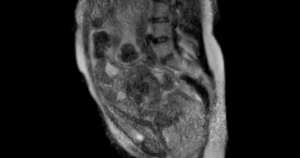

Diễn tiến tích cực rõ rệt khi anh H. tỉnh táo hoàn toàn, không còn rối loạn nhịp thất, chức năng tim hồi phục tốt và có thể ngừng ECMO. Sau 7 ngày điều trị, tình trạng sức khỏe gần như ổn định hoàn toàn, đủ điều kiện xuất viện. Kết quả chụp cộng hưởng từ tim sau đó xác định tình trạng viêm cấp tính trong cơ tim và màng ngoài tim, phù hợp với chẩn đoán viêm cơ tim tối cấp.

Chia sẻ thêm về ca bệnh trên, BS Nguyễn Thanh Thảo, khoa Hồi sức Tim mạch, Bệnh viện Nhân Dân Gia Định cho rằng, không phải người bệnh nào cũng may mắn được phát hiện sớm và cấp cứu kịp thời như trường hợp này. Với hình ảnh viêm lan tỏa trên cộng hưởng từ tim, người bệnh cần được theo dõi sát, tầm soát các đột biến gene liên quan đến bệnh cơ tim và cân nhắc sinh thiết cơ tim nếu tình trạng viêm kéo dài. Đặc biệt, bệnh nhân cần hạn chế gắng sức trong ít nhất 3 tháng đầu để tránh nguy cơ rối loạn nhịp tái phát và đột tử.